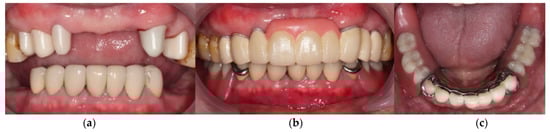

3. Results